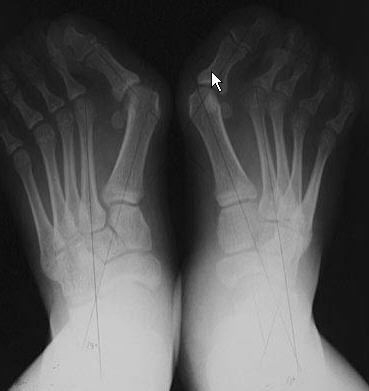

MTP arthrodesis